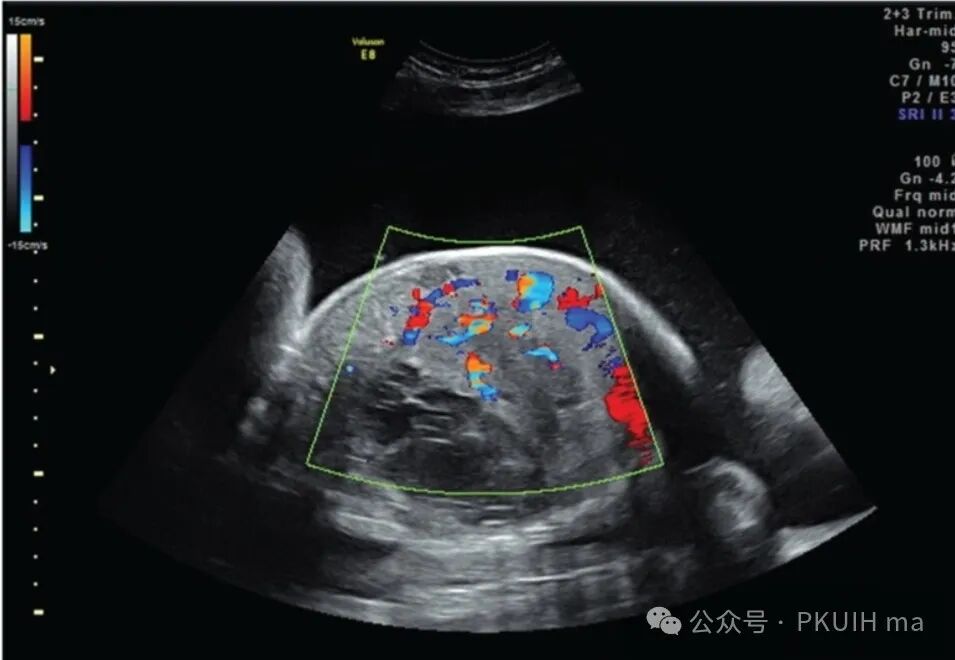

上图是一例在系统排畸时发现的肝局部回声不均并血流异常丰富杂乱,初步考虑肝内动静脉瘘或者是血管瘤,目前一直在随访中。